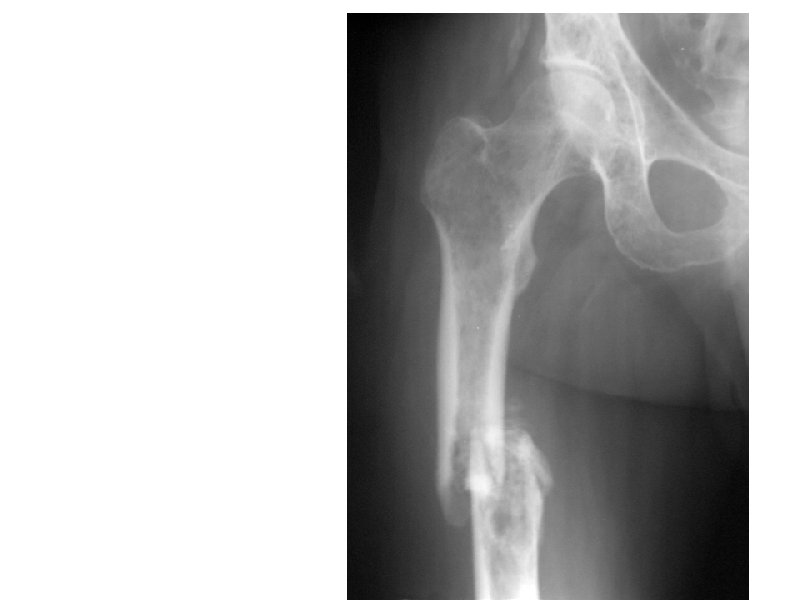

Клинические проявления ММ • Множественные остеолитические очаги Поражение костей повреждения плоских костей и эпифизов трубчатых костей • Диффузный остеопороз (остеопения) • Костные переломы • Уменьшение роста (вертебральный коллапс) Эффекты, ассоциированные с остеодеструкцией Внекостные плазмацитомы • Болевой синдром у 20 -40% Гиперкальциемия ( утомляемость, жажда, тошнота, запоры, повреждение почек, полиурия, сонливость, судороги, кома) • Гиперкальцийурия • Вовлечение мягких тканей преимущественно в области головы/шеи, очаги в печени, почках,

А- рентгенограмма, В- мультидетекторная КТ (МДКТ), Смагнитнорезонансная томография (МРТ)

А-ренгенограмма, В-МДКТ